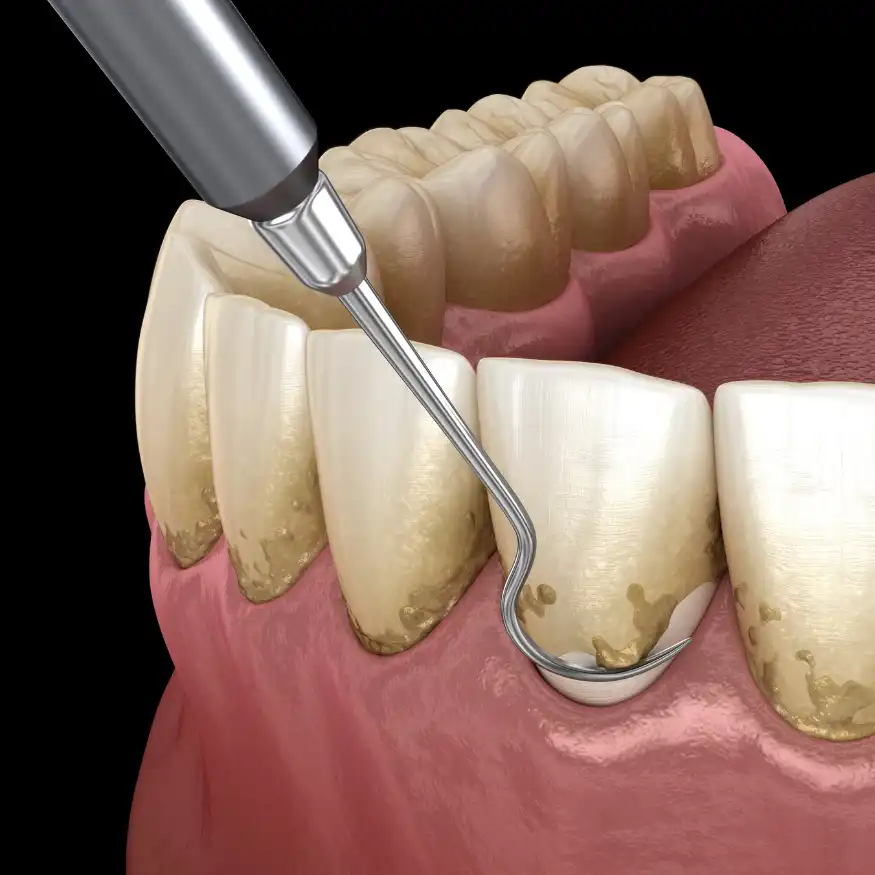

Fase Higiénica – Profilaxis

La profilaxis es una limpieza profunda que elimina la placa bacteriana, el sarro y las manchas superficiales de los dientes. Este procedimiento no solo es fundamental para una sonrisa brillante, sino que también es clave en la prevención de problemas dentales mayores.

Beneficios

Realizar profilaxis regularmente reduce el riesgo de caries y enfermedades periodontales. Además, mejora el aliento y elimina la acumulación de sarro que no se puede retirar con el cepillado diario.

Proceso

Durante la profilaxis, el odontólogo utiliza herramientas de ultrasonido y otros instrumentos para eliminar el sarro. Luego, se pulen los dientes y, en algunos casos, se aplica flúor para reforzar el esmalte. Se recomienda realizar este procedimiento cada seis meses.